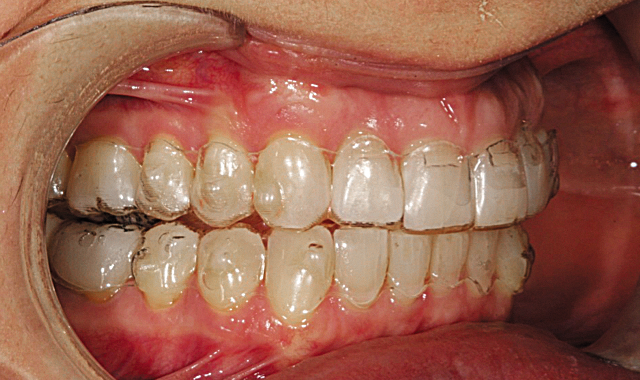

This particular case called for 29 upper and lower Aligners. Aligner fit was perfect and along with a very compliant patient the treatment progressed very smoothly. Pictured here are aligners #27 illustrating the accurate fit throughout treatment (Figs. 11-13).

Our Invisalign treatment led to a very successful clinical result. The crowding and the asymmetries of tooth position, arch form and gingival levels were beautifully corrected (Figs. 14-16).